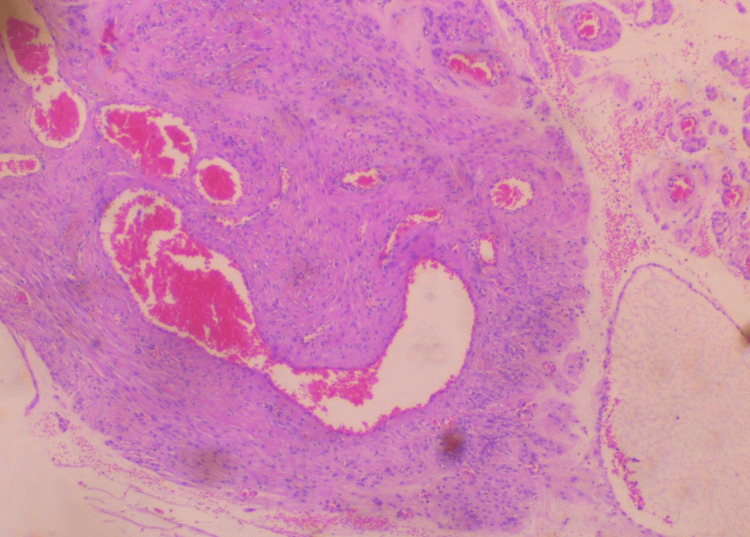

Surgery was completed without significant blood loss. Histological examination of the surgical specimen confirmed the diagnosis of extracervical leiomyoma of the uterus. Microscopic examination of the tumor revealed mild to moderate cellularity, with the absence of mitoses, necrosis, and atypia. In addition, vitrification of the stroma and vascular congestion, probably due to compression, were found in some places (Figures 5-6).

Figure 5. Histological image of extracervical leiomyoma of the uterus.

Moderate cellularity, with the absence of mitoses, necrosis, and atypia, is depicted

Figure 6. Histological image of extracervical leiomyoma of the uterus.

Vitrification of the stroma and vascular congestion, probably due to compression, is depicted